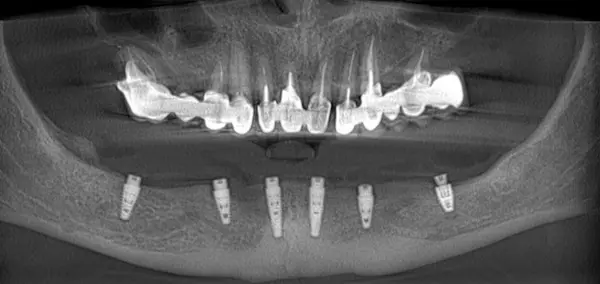

Сканы КТ имплантации зубов, 2026-04-18

Скан КТ, 2026-04-18

Сканы КТ имплантации зубов, 2026-04-18

Скан КТ имплантации зубов, 2026-04-17

Сканы КТ имплантации зубов, 2026-04-18

KT: имплантация зубов DentalKnysh, 2025-01-03, сканы

KT: имплантация зубов DentalKnysh, 2025-01-03, сканы

KT: имплантация зубов DentalKnysh, 2025-01-03, сканы

КТ имплантации зубов в DentalKnysh (10 имплантов), 2023-11-03

С 2023-09-05 по 2023-09-09 сканы КТ от 6 до 12 имплантов в DentalKnysh (4 фото):

Синуслифтинг и имплантация зубов, 6 имплантов, all-on-6, КТ скан 1, 2023-08-31

Фото отчет Имплантация зубов, 6 имплантов, КТ скан 3, 2023-08-31

Фото отчет Имплантация зубов, 8 имплантов, all-on-4, КТ скан 1, 2023-08-31